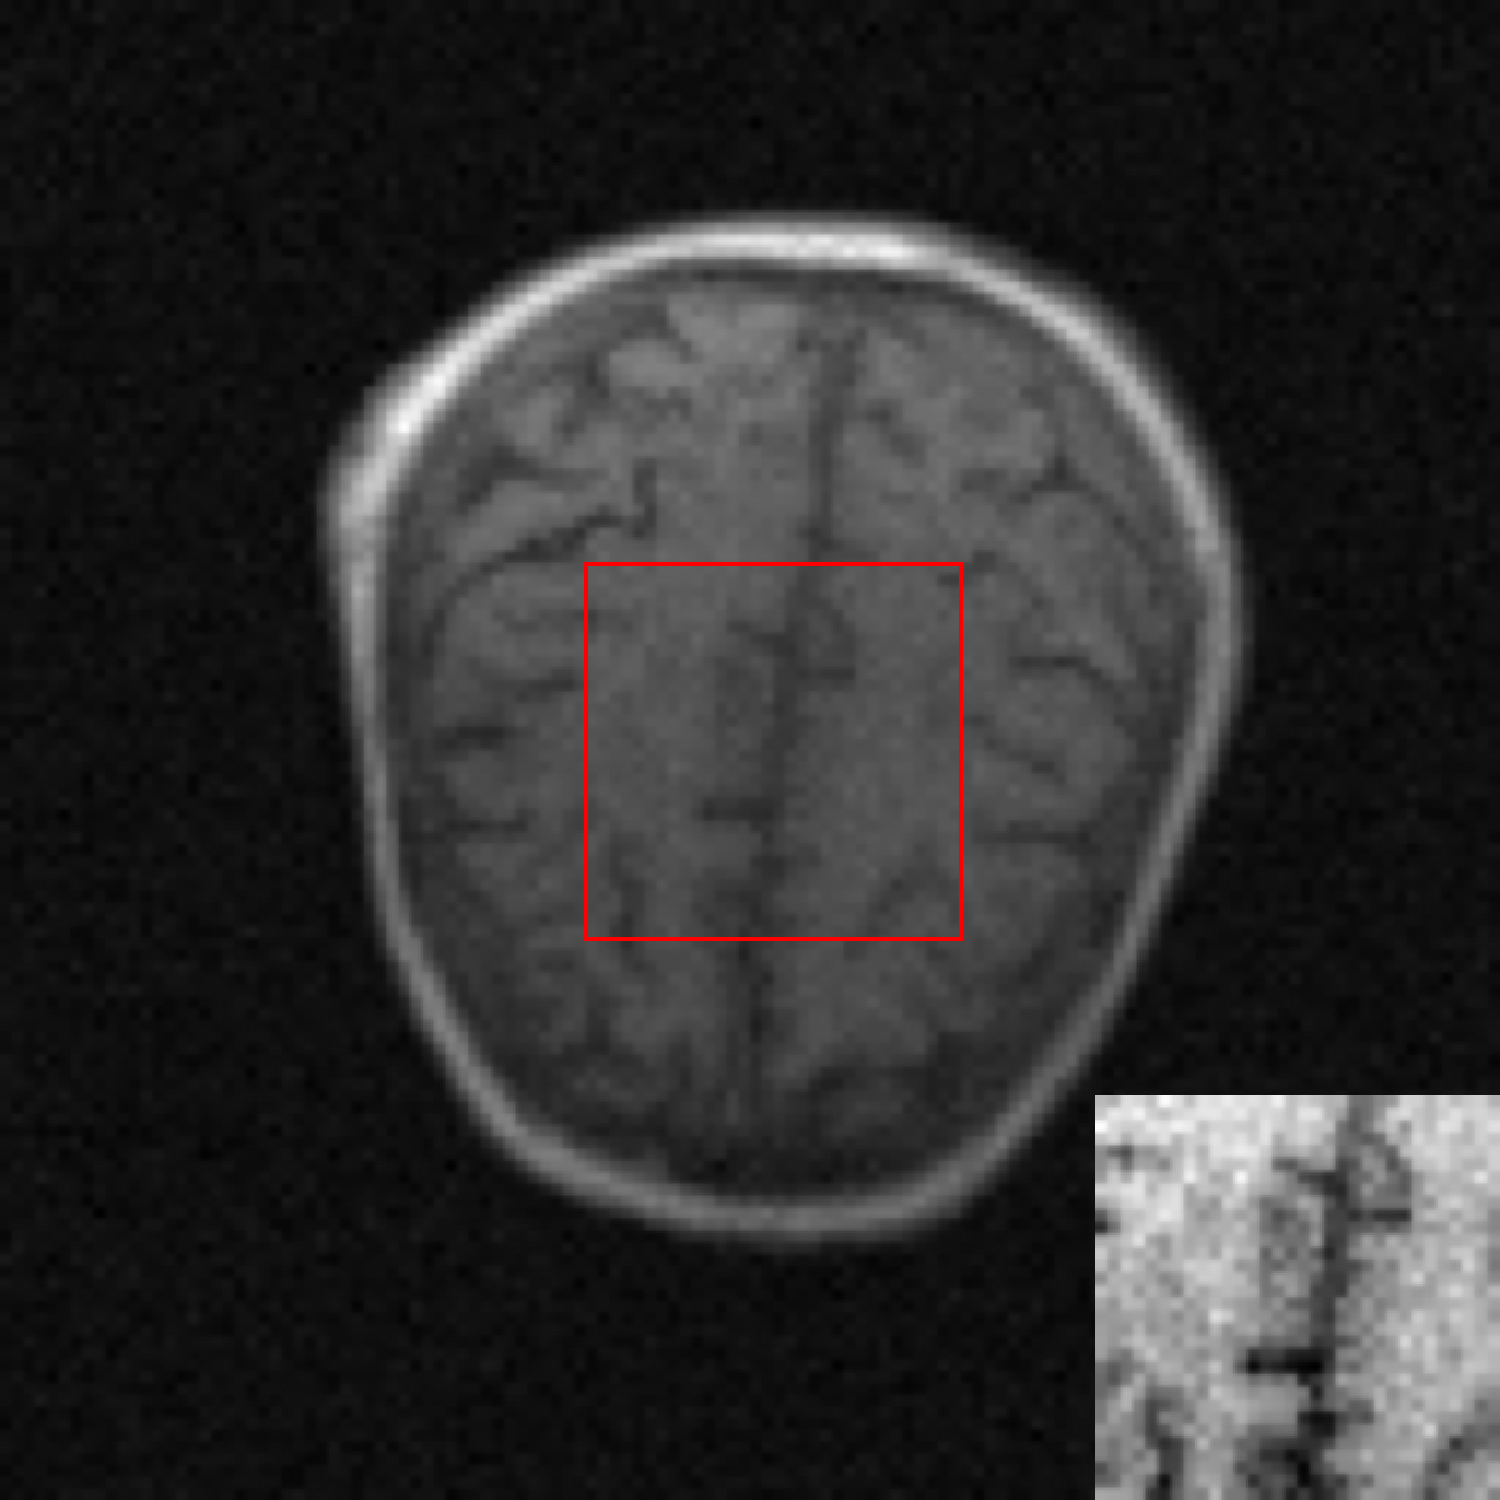

A simulation study was conducted. MR brain images in the NYU fastMRI Initiative database [11] (https://fastmri.med.nyu.edu/) were employed to form an ensemble of images that depict object properties sampled from the unknown SOM. Specifically, 3000 T1 weighted brain MR images corresponding to the magnetic field strength of 3T were selected, and these 3000 images were resized to the dimension of to be employed as real object images. Fully-sampled MR k-space data of these 3000 object images were simulated, and complex Gaussian noise were added to the k-space data. These 3000 noisy k-space measurement data formed the training dataset. An example of MR brain images, its corresponding k-space measurement data and the reconstructed image (i.e., IDFT of k-space measurement data) are shown in Fig. 2.